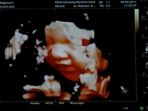

Jika kebanyakan calon ibu ingin mengetahui jenis kelamin bayinya saat masih di dalam perut, beda halnya dengan artis yang satu ini.

Mereka biasanya melakukan hal itu saat usia kandungannya memasuki usia enam sampai sembilan bulan.